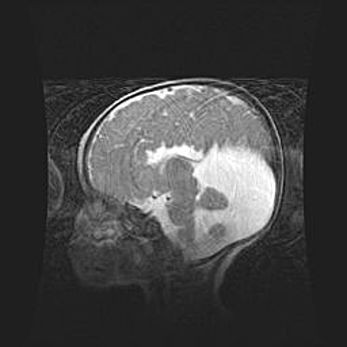

Сообщающаяся гидроцефалия. Кистозная энцефаломаляция головного мозга.

Возраст: 3 месяца 4 дня

Вес: 3100 г

Пол: женский

Окружность головы: 34 см

Срок гестации: 31 неделя

Кистозная энцефаломаляция головного мозга - одна из форм поражения головного мозга в детском возрасте. Характеризуется возникновением множественных и распространённых кист в коре, белом веществе и подкорковых образованиях головного мозга у плодов, новорождённых и детей раннего возраста. Развитие кистозной энцефаломаляции связано с внутриутробной асфиксией и гипотонией, родовой травмой, тромбозом синусов, пороками развития сосудов, инфекциями, сепсисом и другими причинами. Наиболее значимые инфекционные агенты: вирусы простого герпеса, цитомегалии, краснухи, токсоплазмы, энтеробактерии, золотистый стафилококк и другие.